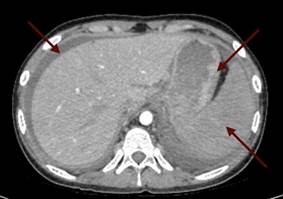

При поступлении - жалобы на отсутствие аппетита, общую слабость, нехватку воздуха без кислородной поддержки. Рост 170 см, вес 67 кг, ИМТ (индекс массы тела) - 23,18. При физикальном обследовании отмечалась бледность кожи, ЧСС – 82 удара в минуту, артериальное давление 120/80 мм рт. ст., SpO2 98-99%. Аускультативно выслушивалось ослабленное везикулярное дыхание в нижних отделах легких, больше слева. Была болезненность при пальпации живота в левой подвздошной области, в паховой области слева. Симптомы раздражения брюшины были отрицательные, при пальпации объемное образование в брюшной полости не определялось. Симптом поколачивания по поясничной области был положительный слева. По результатам УЗИ органов брюшной полости были выявлены признаки утолщения стенок лоханок обеих почек, признаки спленомегалии, в области ворот лимфоузлы размером до 22х15 мм, лимфаденопатии парааортальных лимфатических узлов размером 27х17 мм, реактивных изменений печени и поджелудочной железы; свободная жидкость за маткой, над мочевым пузырем межпетельно, по правому латеральному каналу, поддиафрагмально слева; свободная жидкость в плевральных полостях. На обзорной рентгенографии органов грудной полости выявлен двусторонний экссудативный плеврит. На ЭКГ снижение вольтажа зубцов ЭКГ в левых грудных отведениях. В общем анализе крови выявлен нейтрофильный лейкоцитоз до 9,09х109/л, снижение уровня гемоглобина до 104 г/л, ускорение СОЭ до 44 мм/час. В биохимическом анализе крови - повышение лактата до 3,43 ммоль/л, СРБ до 68,6 мг/л, амилазы до 102,28 Ед/л, липазы до 224.73 Ед/л. В коагулограмме – гипокоагуляция. В анализе мочи – протеинурия до 1 г/л. По тяжести состояния ребенок был госпитализирован в отделение интенсивной терапии. При обследовании по данным КТ брюшной полости (рис. 1) было выявлено увеличение парааортальных лимфатических узлов до 38х14 мм, объемное образование стенки желудка (в области большой кривизны - неравномерное утолщение стенки большой кривизны желудка до 25 мм на протяжении 65 мм, увеличение селезенки в размерах до 123х45х135 мм), асцит, свободная жидкость в полости таза.

Рис. 1. Компьютерная томограмма органов брюшной полости пациентки с раком желудка: объемное образование стенки желудка (1), свободная жидкость в полости таза (2)